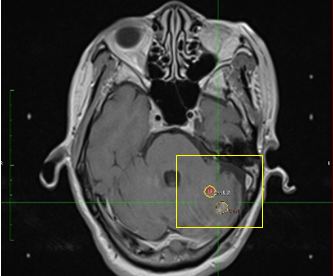

Hình 21: Hình ảnh đặt kế hoạch điều trị cho 2 tổn thương trong một ma trận

Ma trận tính toán được thể hiện (ma trận màu đỏ được chọn). Các shot có thể chỉ được đặt trong ma trận.

Bệnh nhân Ngô Hữu V.; nam, 60 tuổi. Chẩn đoán: Ung thư phổi di căn tiểu não. Chỉ định xạ phẫu: dao gamma quay (RGK) liều 22Gy”